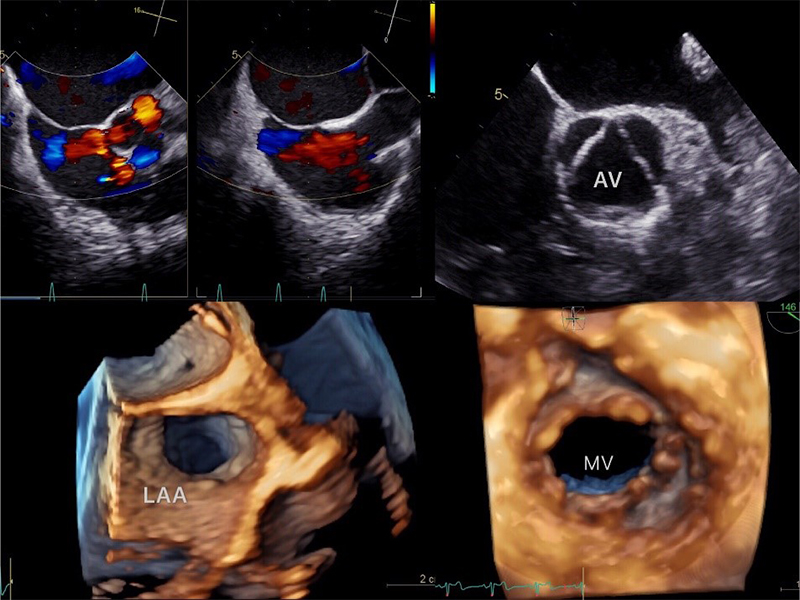

GE Vivid E95 6VT-D